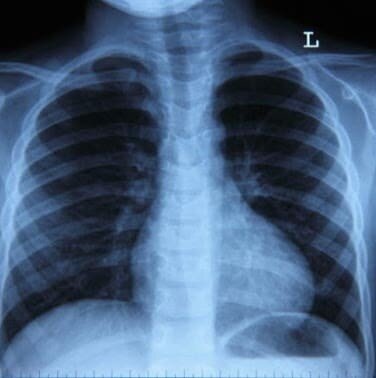

Рентген легких при пневмонии

Рентгенография является одним из самых распространенных методов первичного выявления различных заболеваний дыхательных путей и назначается гораздо чаще других видов обследования – магнитно-резонансной или компьютерной томографии. Рентгенография может быть обзорной в тех случаях, когда необходимо рассмотреть легкие в целом, или прицельной, когда исследуется фрагмент органа. Разновидностью рентгенографического исследования является обычная флюорография. В ходе нее изображение с рентгенографического аппарата фотографируется на пленку. Подобная диагностика является самой доступной для пациентов по причине ее дешевизны, но и самой неточной. Четкость флюорограмм в несколько раз меньше рентгеновских снимков и не позволяет выявить многих проблем легких.

В настоящее время более активно используется цифровой или четырёхсторонний рентген легких для диагностирования различных патологий бронхолегочной системы. По данным рентгенограмм врач в 80% случаев сможет сказать, есть ли признаки воспаления легких, однако четко и точно визуализировать очаги поражения сможет только компьютерная томография.

Чаще всего врач выявляет пневмонию у пациента после изучения результатов клинико-рентгенологических обследований. Если их бывает недостаточно для постановки диагноза, а также при наличии сомнений или малоинформативности данных, врач рекомендует пройти КТ диагностику. Стоит заметить, что рентген и КТ легких и бронхов – это разные рентгенологические методы диагностики. При сравнении снимков можно отметить их существенную разницу.

КТ легких Рентген легких

КТ легких однозначно обладает большей чувствительностью, и потому ее информативная точность намного выше. При помощи компьютерного томографа можно выявить даже незначительные отклонения за счет создания трехмерных изображений, которые на рентгене могут не отобразиться из-за наложения одних органов на другие. Такая диагностическая чувствительность очень важна при диагностике пневмонии на ранней стадии, когда есть очаги воспаления размером в 2-5 мм.

С точки зрения безопасности рентгенография - это форма обследования с меньшей лучевой нагрузкой, поэтому именно ее, а не КТ, используют для первичного скринингового сканирования.